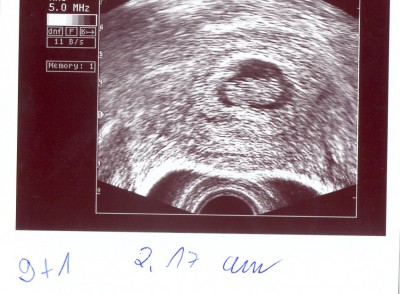

So, ich werde jetzt mal meine US-Bildchen scannen und dann ins Album stellen